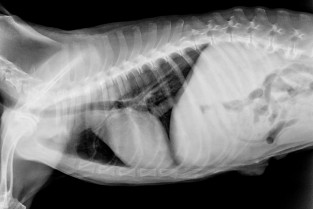

Quel dommage de ne pas exploiter complètement tout ce que l'on peut voir sur des clichés thoraciques. À partir de cas concrets, nous allons explorer toutes les facettes de ces clichés et les pièges à éviter.

- évaluer la qualité d'un cliché ;

- connaitre l'intérêt de la radiographie thoracique suivant les suspicions cliniques ;

- reconnaitre les pièges des clichés.